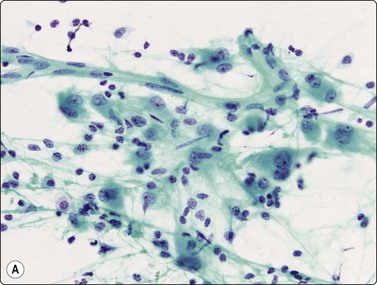

image

Fig. 8.3 Alveolar macrophages

Loose aggregates and dispersed cells with rounded nuclei, small nucleoli, and abundant finely vacuolated cytoplasm (Pap, HP).

Normal lung yields a population of macrophages widely dispersed over the slide (Fig. 8.3); these contain small particles of brown or black particulate matter, some of which is inhaled dust, especially in smokers. Many hemosiderin-laden macrophages usually imply tissue or blood breakdown near the lesion and may add to a suspicion of pulmonary infarction should the clinical background be appropriate.